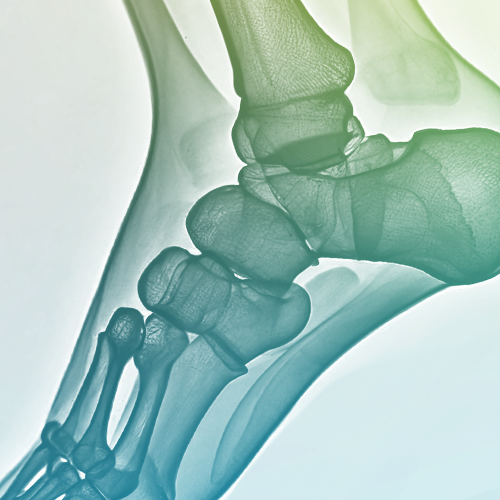

Ankle Osteoarthritis

Painful condition affecting younger patients significantly; 60% have prior injury history. Treatment ranges from non-surgical (orthotics, physical therapy, injections) to surgical corrections (joint-preserving or joint-sacrificing procedures like arthrodesis and prosthesis implantation).

Ankle Surgery

Medical procedure addressing various ankle joint issues. Includes thorough assessment followed by personalized treatment selection considering patient-specific needs for stability and proper function.